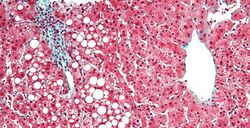

Micrograph of periportal hepatic steatosis, as may be seen due to steroid use, trichrome stain

Micrograph of inflamed fatty liver (steatohepatitis)

Severe fatty liver is sometimes accompanied by inflammation, a situation referred to as steatohepatitis. Progression to alcoholic steatohepatitis (ASH) or non-alcoholic steatohepatitis (NASH) depends on the persistence or severity of the inciting cause. Pathological lesions in both conditions are similar. However, the extent of inflammatory response varies widely and does not always correlate with degree of fat accumulation. Steatosis (retention of lipid) and onset of steatohepatitis may represent successive stages in FLD progression.[23]

Liver disease with extensive inflammation and a high degree of steatosis often progresses to more severe forms of the disease.[24] Hepatocyte ballooning and necrosis of varying degrees are often present at this stage. Liver cell death and inflammatory responses lead to the activation of hepatic stellate cells, which play a pivotal role in hepatic fibrosis. The extent of fibrosis varies widely. Perisinusoidal fibrosis is most common, especially in adults, and predominates in zone 3 around the terminal hepatic veins.[25]